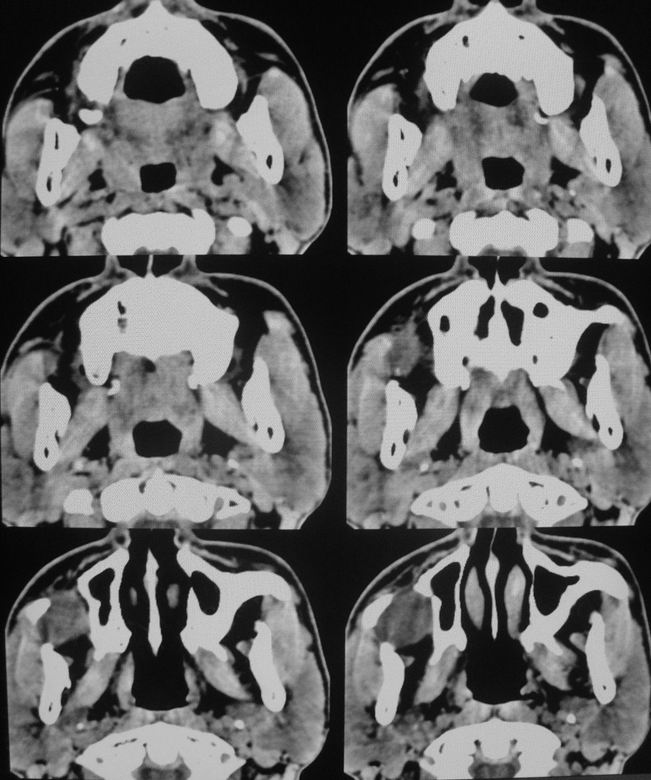

以下是引用zsl6918在2008-5-6 14:41:00的发言:[br]右侧颞下窝内囊性占位(增强未见强化),同侧上颌窦受压变形移位,提示慢性过程。右侧上颌骨局限性吸收破坏,提示良性病变。

以下是引用xuhuihong在2008-5-6 14:57:00的发言:[br]右侧颞下窝内囊性占位(增强未见强化),同侧上颌窦受压变形移位骨质吸收变薄,提示慢性过程。右侧上颌骨局限性吸收破坏,提示良性病变。考虑神经源性肿瘤可能,期待结果。